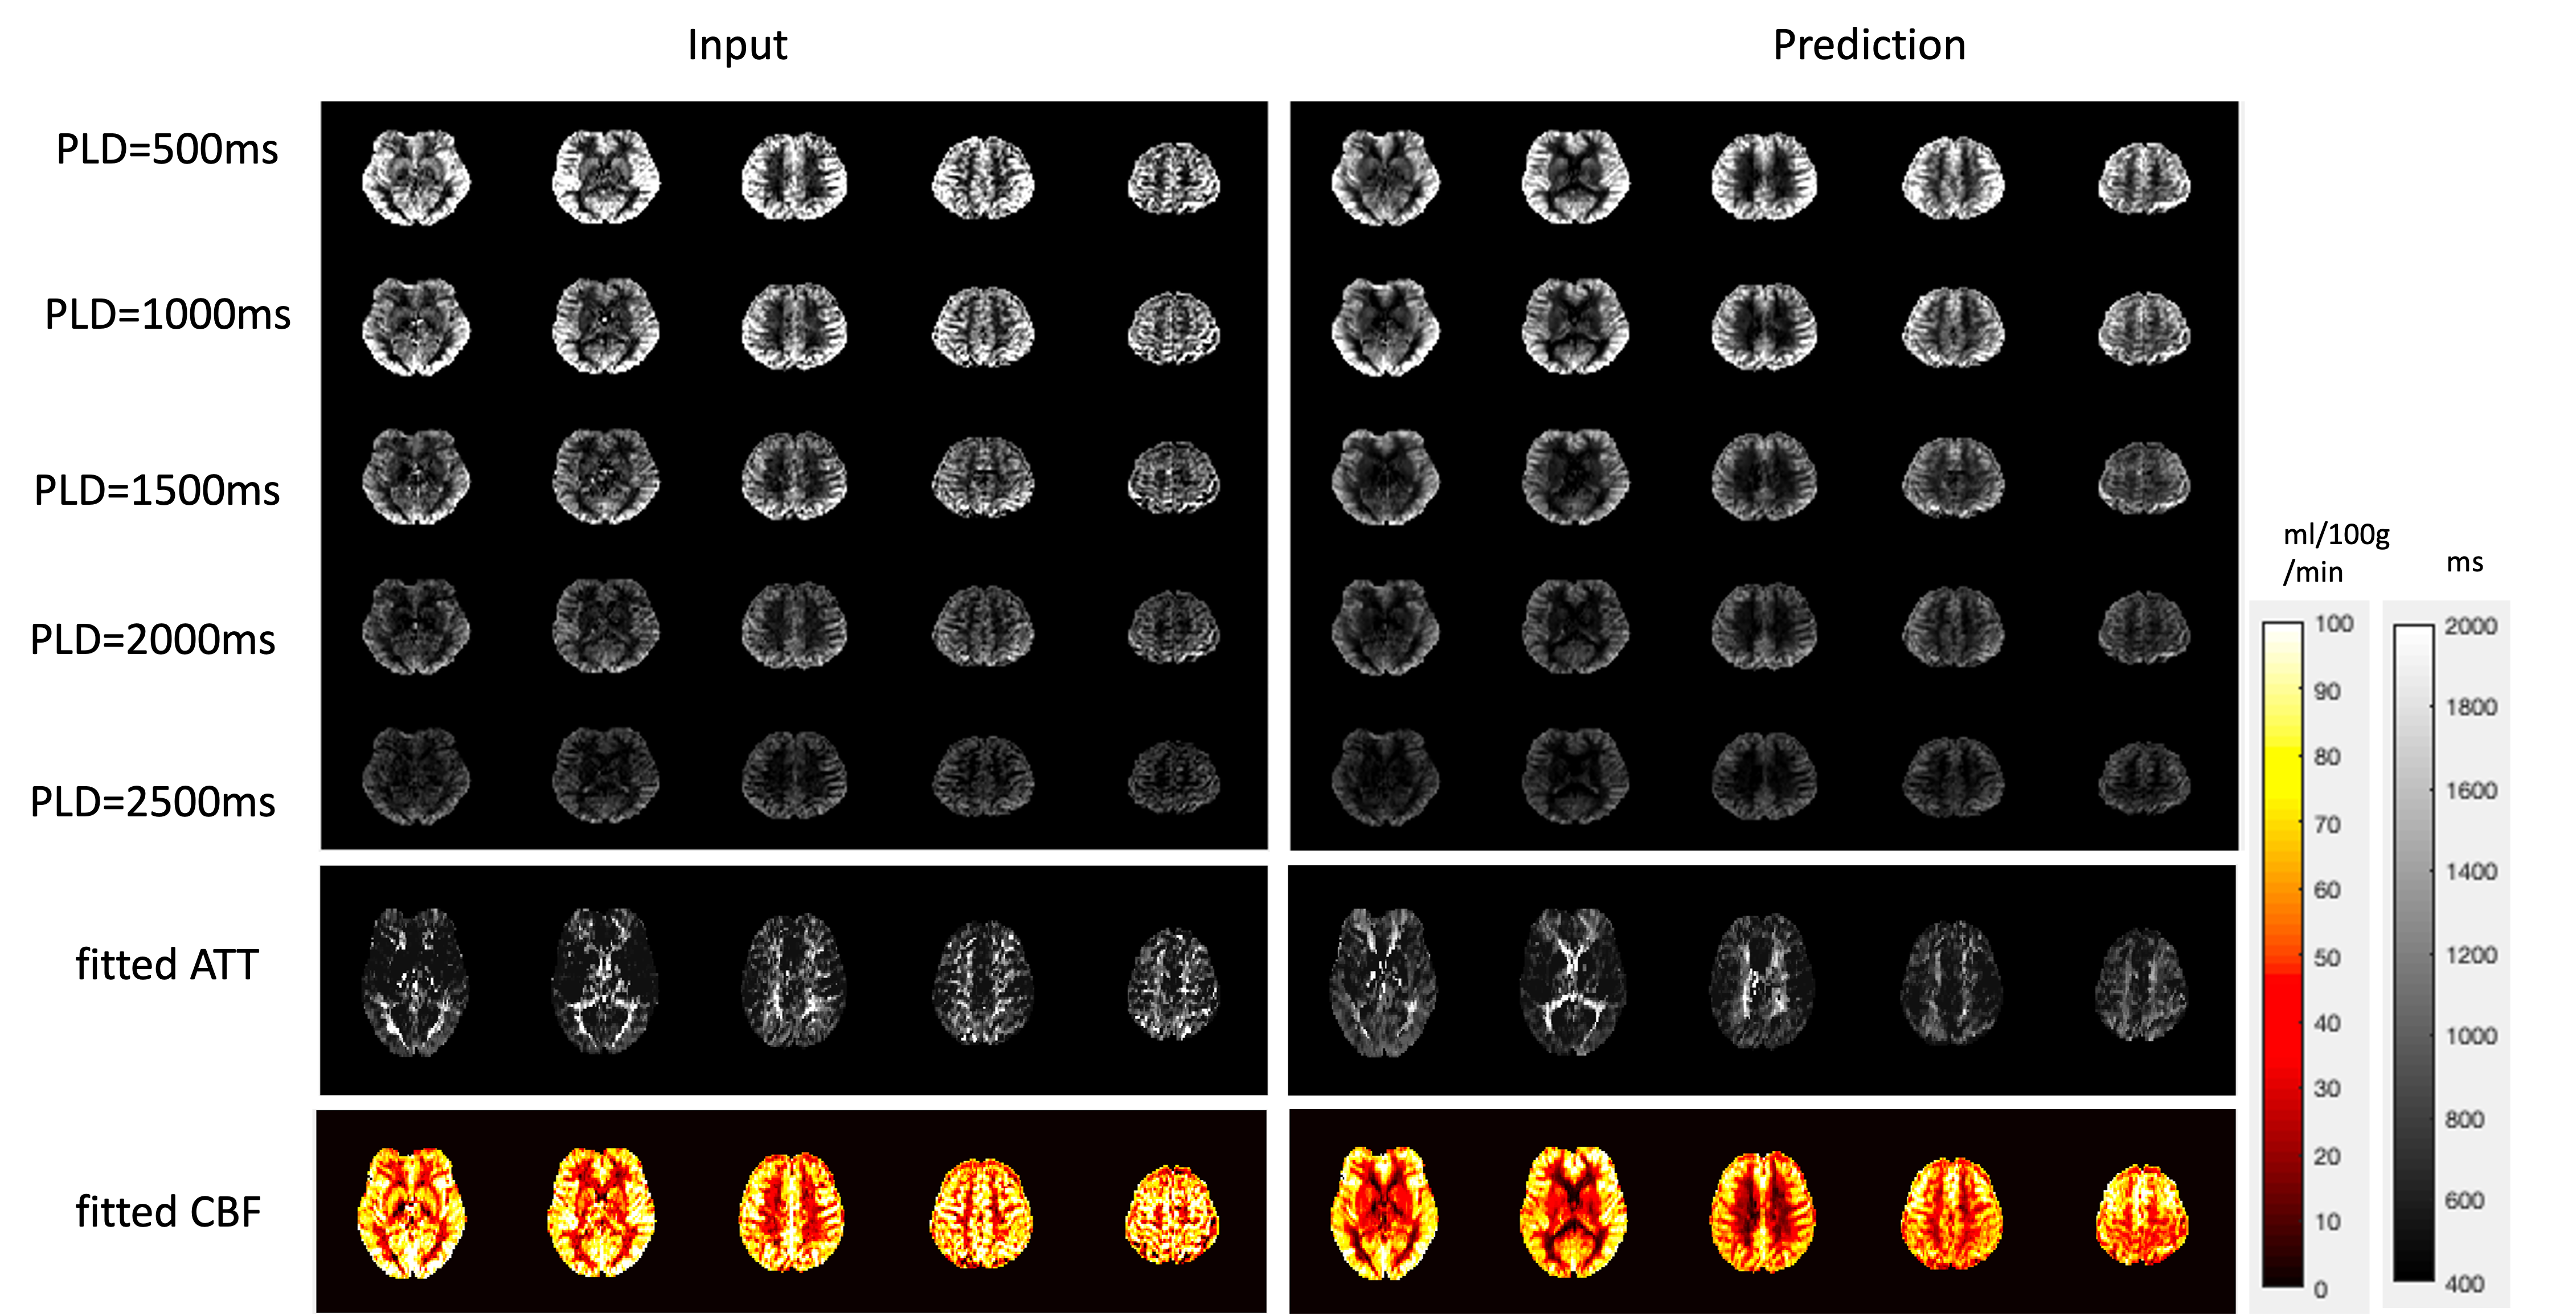

Figure 2 shows the results for the first test dataset, the image for the DL prediction has improved SNR compared to the input. The similarities metrics are also consistent with the visual quality, SSIM and PSNR after DL denoising were improved by 2% and 7.6%, while spatial and temporal SNR were improved by 181% and 134% respectively. Figure 3 shows the results for the second dataset, SSIM and PSNR were improved by 1.4% and 3.9%, while spatial and temporal SNR were improved by 71% and 42% respectively. Figure 4 shows the results for the multi-delay dataset. DL prediction has improved the SNR for perfusion images at each PLD, and improved SNR for the fitted CBF and ATT maps. Figure 5a shows that the global CBF values calculated from the DL prediction is highly consistent with those from the single-delay input images. Figure 5b and 5c show that the fitted CBF and ATT values from the DL predicted multi-delay perfusion images are also consistent with those fitted from the input images.

Figure 4. The input and prediction on the multi-delay test dataset. First five rows show the input and DL denoised perfusion images of the 5 different post labeling delays. The DL denoised perfusion images have better SNR in all 5 PLDs. The bottom two rows show the fitted CBF and ATT maps from the input/prediction multi-delay perfusion images. The fitted perfusion images are quite consistent with the input image.